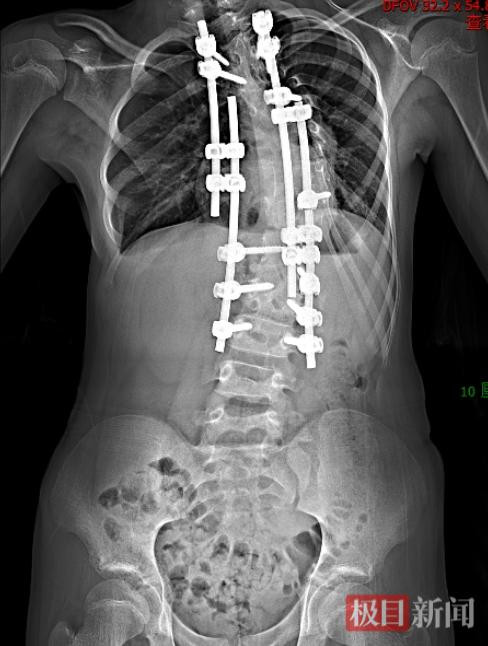

2025年,可可年满12岁,胸腔、胸廓已基本发育成熟,周治国团队决定对最严重的顶椎“动手”,他们利用3D打印技术,1:1还原了畸形的脊柱,并制定了截骨矫正的手术方案。

整场手术进行了10个多小时,周治国团队避开脊柱周围的神经和血管,对可可畸形弯曲最严重且最突出的顶椎进行截骨、重整、固定。手术结束时,可可脊柱的侧弯度数从72度改善到30度,她可像正常人一样生活。

最后一次手术后,孩子脊柱侧弯的状态有了较大改善